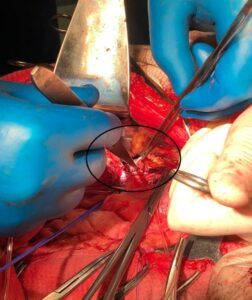

При ультразвуковом исследовании вен системы НПВ —флотирующийнеокклюзирующий опухолевый тромб супраренального, позадипеченочного отдела НПВ размером 7х2х1 см, с верхушкой на 1 см ниже устья впадения печеночных вен, с явлениями умеренной флотации (рис. 1). Надпеченочный, наддиафрамальный, инфраренальный отдел НПВ проходимы, также отмечена проходимость на всем протяжении магистральных поверхностных и глубоких вен нижних конечностей и таза.

Рис. 1. УЗ-сканограмма нижней полой вены пациента Г. Красными стрелками указан флотирующий опухолевый тромб в позадипеченочном отделе нижней полой вены.